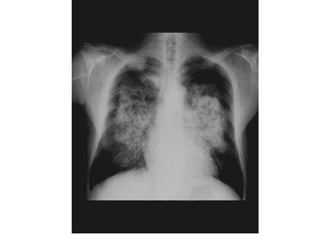

Patrón alveolar difuso EDEMA

PULMONAR

PULMONAR(Distress)